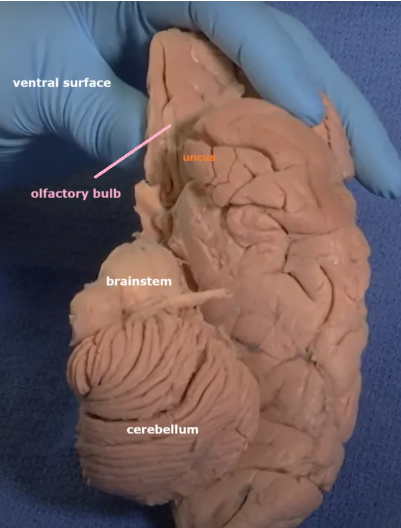

The purple hippocampus is visualized tracing the ventricular system (turquoise).